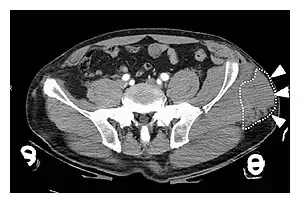

| A Morel-Lavallée lesion is a closed traumatic soft-tissue degloving injury, caused by separation of the hypodermis from the underlying fascia.[1] It most frequently occurs in the peritrochanteric region along the proximal lateral thigh,[1] such as in this CT scan. |